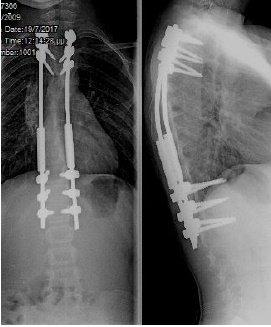

Σύνθετες παραμορφώσεις της σπονδυλικής στήλης, όπως είναι η σκολίωση και η κύφωση, ακόμη και σε περιπτώσεις παιδιών με συγγενείς ανωμαλίες ή νευρομυϊκές παθήσεις, αντιμετωπίζονται χειρουργικά και στις νεαρότερες ηλικίες. Τα σύγχρονα συστήματα σπονδυλοδεσίας επιτρέπουν τη διόρθωση της παραμόρφωσης, με παράλληλη επιμήκυνση της σπονδυλικής στήλης, ενώ το παιδί συνεχίζει να αναπτύσσεται και να ψηλώνει. Αποτέλεσμα είναι τα παιδιά – αλλά και οι οικογένειές τους - να αντιμετωπίζουν με ασφάλεια και να αφήνουν οριστικά πίσω τους ένα δύσκολο πρόβλημα, όπως είναι μια παραμόρφωση της σπονδυλικής στήλης, συνεχίζοντας με μια φυσιολογική ανάπτυξη και ακολουθώντας όλες τις δραστηριότητες των παιδιών της ηλικίας τους.